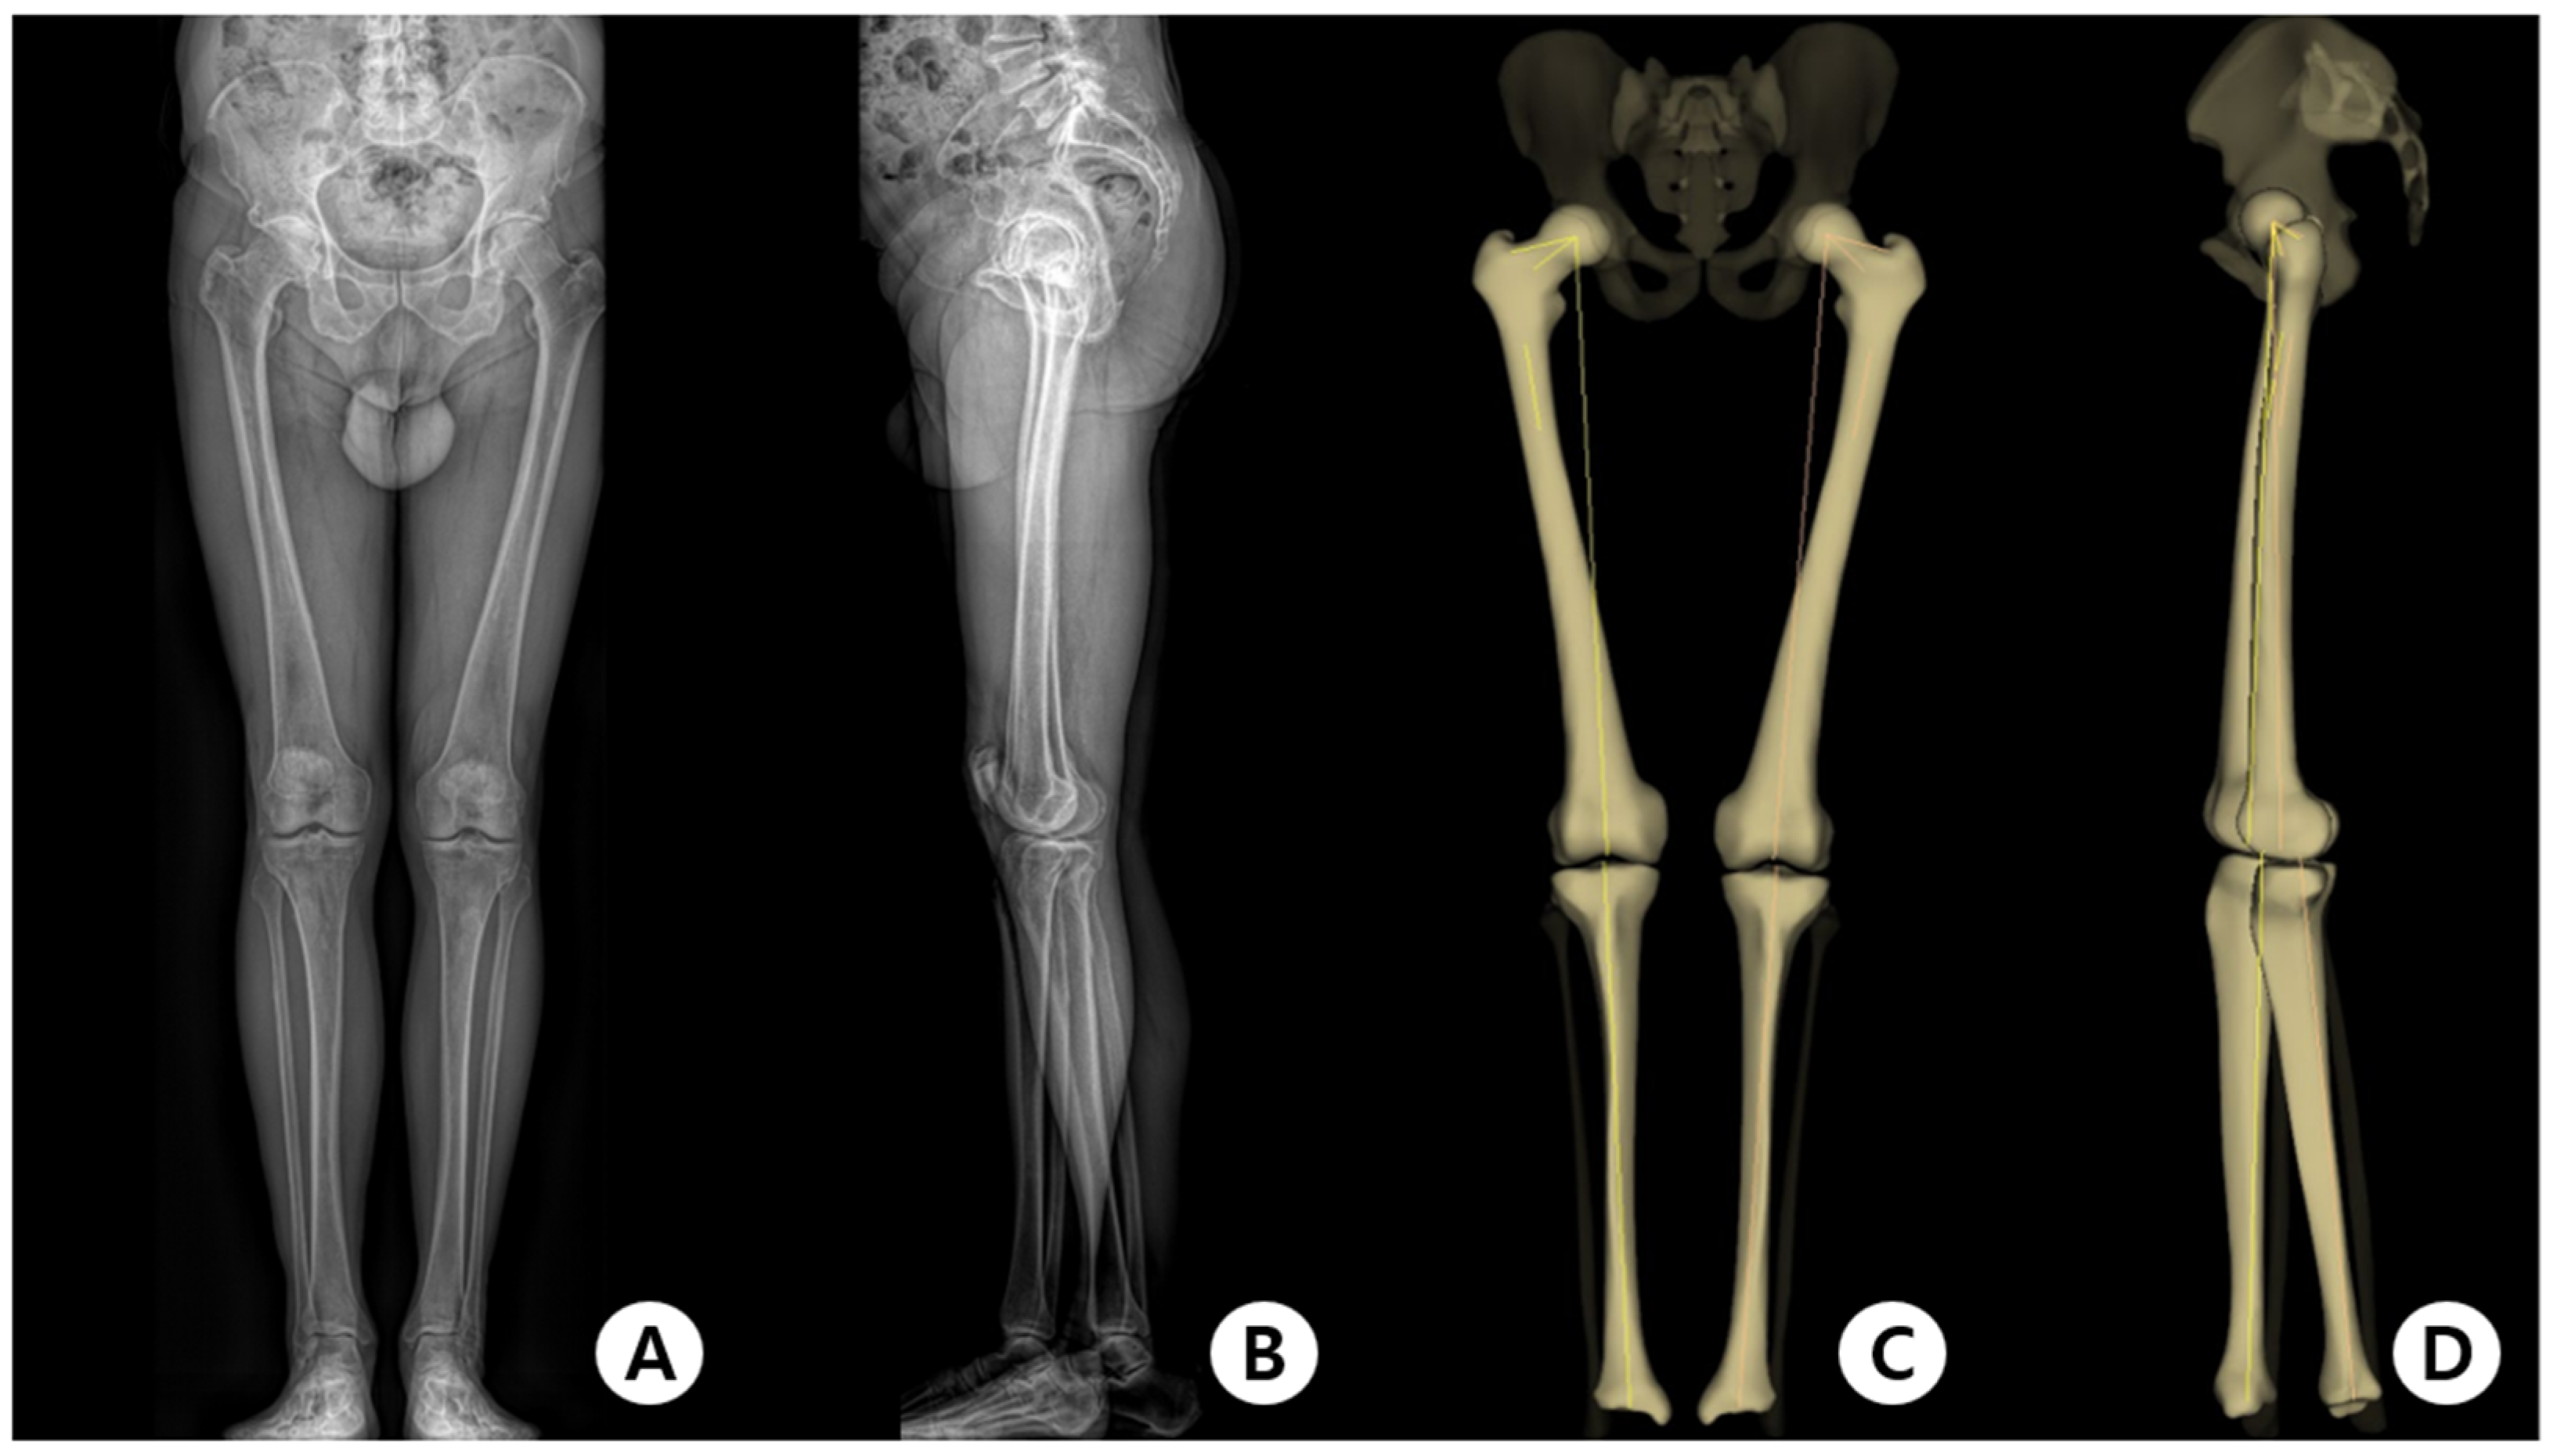

2.2. Evaluation Methods

2.3. Measurement of Parameters and Clinical Outcomes